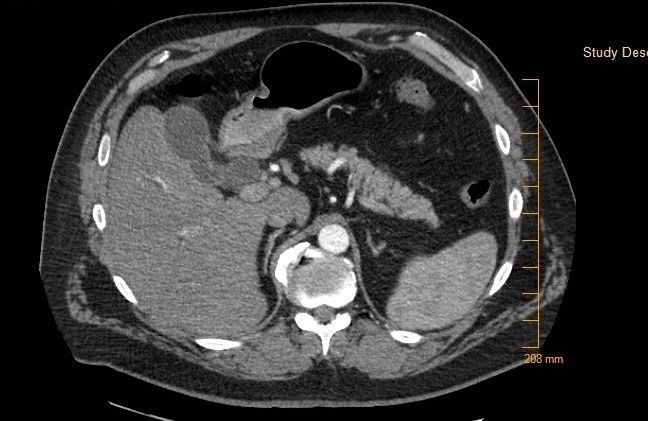

At his next visit with his PCP, however, he complained of pruritus, loss of appetite, 30 lb weight loss, weakness, increased yellowing of eyes, and worsening abdominal pain for 3 – 4 days. He was sent emergently to the ED, and a repeat CT scan of the abdomen/pelvis showed diffuse fatty infiltration of liver, mildly distended gallbladder with intra and extra hepatic biliary ductal dilatation and a common bile duct measuring up to 2 cm. No definitive filling defect was seen within the gallbladder. Ultrasound of the abdomen demonstrated dilated intrahepatic and extrahepatic ductal dilatation and uncomplicated small gallstones within the gallbladder but without choledocholithiasis or a discrete mass identified.

His laboratory values were significant for elevated total and direct bilirubin (22.4 and 15.9 mg/dl). Additional lab values include – an AST (137 U/L) and ALT (232 U/L), and an abnormally elevated Lipid panel with LDL (263 mg/dl), triglyceride (357 mg/dl), and total cholesterol (346 mg/dl). On day three of admission, the patient underwent an endoscopic retrograde cholangiopancreatography (ERCP) with findings significant for multiple gallstones in the common bile duct (Fig. 1 - 4) consistent with Mirizzi syndrome.

Mirizzi syndrome is obstruction of the common hepatic duct from a stone impacted on the gallbladder infundibulum or cystic duct remnant. It has been classified into five variants (Table 1) based on the Csendes 2007 classification.1 It usually presents with right upper quadrant pain, with or without jaundice and fever.2 The most commonly used studies for diagnosing Mirizzi syndrome are the ultrasound, computed tomography (CT), magnetic resonance cholangiopancreatography (MRCP) but the endoscopic retrograde cholangiopancreatography (ERCP) is the most sensitive.3 It is reported to have a 100% sensitivity,3 and as seen in this case can be diagnostic for Mirizzi syndrome.